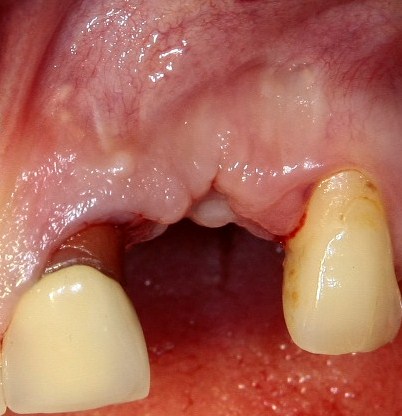

Около трёх лет назад к нам в клинику обратилась пациентка Мария, на момент обращения ей было 45 лет. Её беспокоила ситуация с передними резцами:

В ходе беседы она рассказала, что лечит эти зубы всю сознательную жизнь — их депульпировали («удалили нерв») из-за последствий травмы еще в школьном возрасте, и после этого каждые несколько лет (а то и чаще) ей приходилось перелечивать каналы, менять коронки, вкладки и т. д.

В результате, зубы приобрели очень уж нездоровый вид (см. фото выше). Вдобавок, всё усугубилось существенным снижением качества жизни — коронки и вкладки из зубов постоянно выпадают, десна вокруг них кровоточит при чистке…. Кроме того, Марию не покидает ощущение того, что эти зубы могут просто вывалиться в самый неподходящий момент. Именно это заставило её обратиться в нашу клинику.

Визуальный осмотр:

Подвижность зубов (или коронок) II-III степени косвенно свидетельствует о разрушении периодонтальных связок и стенок лунок зубов. Подвижность является следствием хронического воспаления, когда окружающие зуб ткани остаются без питания и деградируют — и в совокупности это может существенно осложнить сохранение эстетических параметров окружающих имплантат тканей. Степень риска — высокая.

Рецессия десны из-за хронического воспаления — признак запущенного длительного существующего воспалительного процесса, в результате которого разрушается, в том числе, костная ткань. В таких условиях её регенеративная способность, не говоря уже свойствах десны, существенно снижается. Скорее всего, на КЛКТ мы увидим утрату вестибулярной стенки лунки (что объясняет подвижность). Степень риска — высокая.